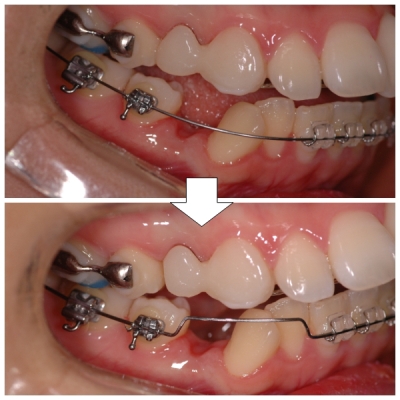

다음으로 오늘 치아교정후기의 메인! 와이어 교체!!

하악 장치 와이어를 한 단계 더 굵은 놈으로~!

아, 이번 철사는 굵기 말고 달라진 것이 또 하나 있어요.

짠! 모양이 업~그레이드~! 피카츄가 라이츄가 될 때 이 느낌이었을까?;;

제 치아 이 송곳니가 많이 누워 있어서,

후에 일으키기 위해서 이렇게 생긴 것이 랍니다.